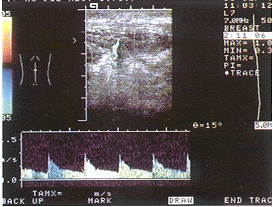

B超诊断腰背部神经纤维瘤1例

患者男 ......